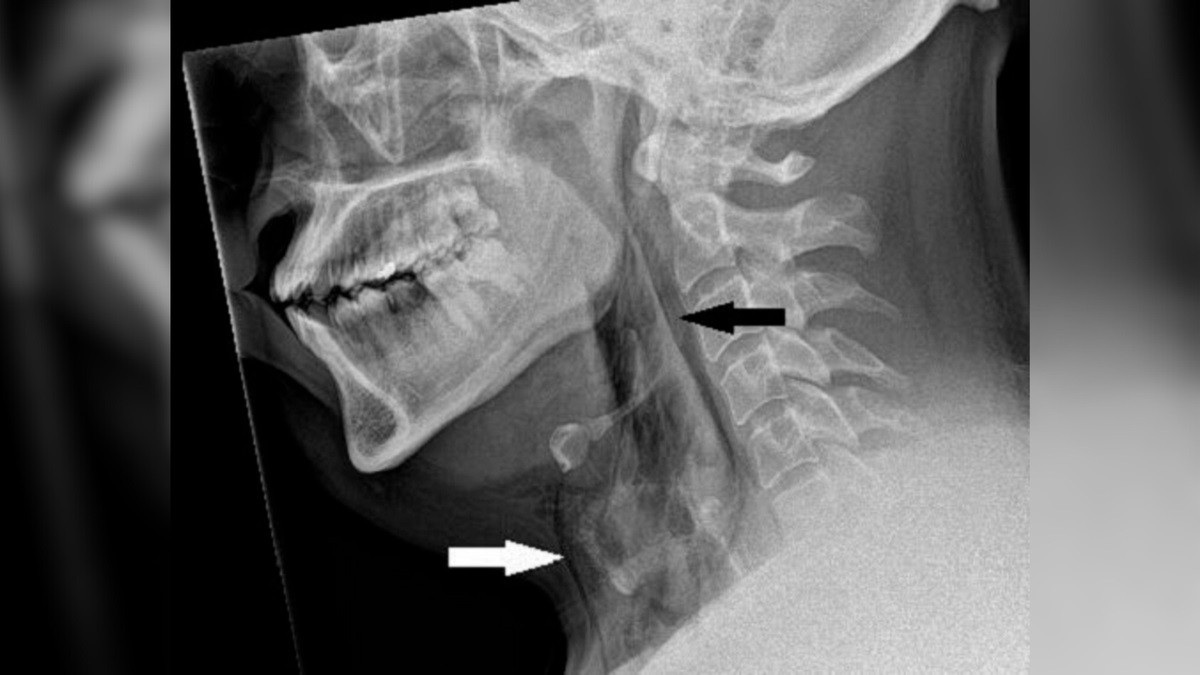

| Phim chụp X-quang cổ của người đàn ông cho thấy anh ta có các túi khí mắc kẹt bên dưới da cổ, như được thể hiện qua các mũi tên ở trên. (Ảnh: Báo cáo trường hợp BMJ 2023) |

Kết quả chụp X-quang cổ cho thấy người đàn ông này bị khí thũng do phẫu thuật , tình trạng không khí bị mắc kẹt dưới các lớp mô sâu nhất bên dưới da. Kết quả chụp cắt lớp vi tính (CT) sau đó cho thấy vết rách nằm giữa xương thứ ba và thứ tư, hay còn gọi là đốt sống, trên cổ của anh ấy. Không khí cũng đã tích tụ trong khoảng trống giữa phổi của anh ấy .